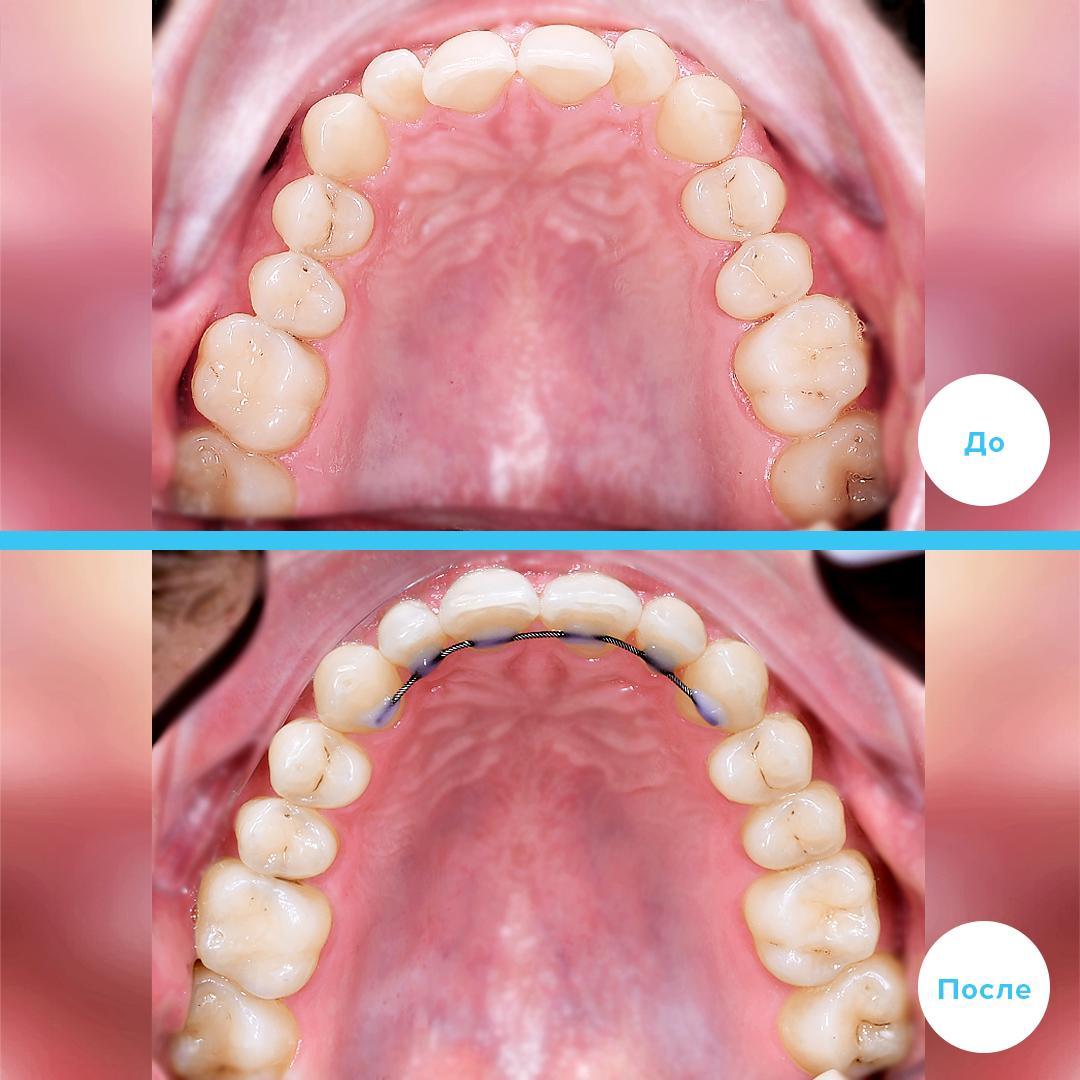

Раздел: Кадры прогресса